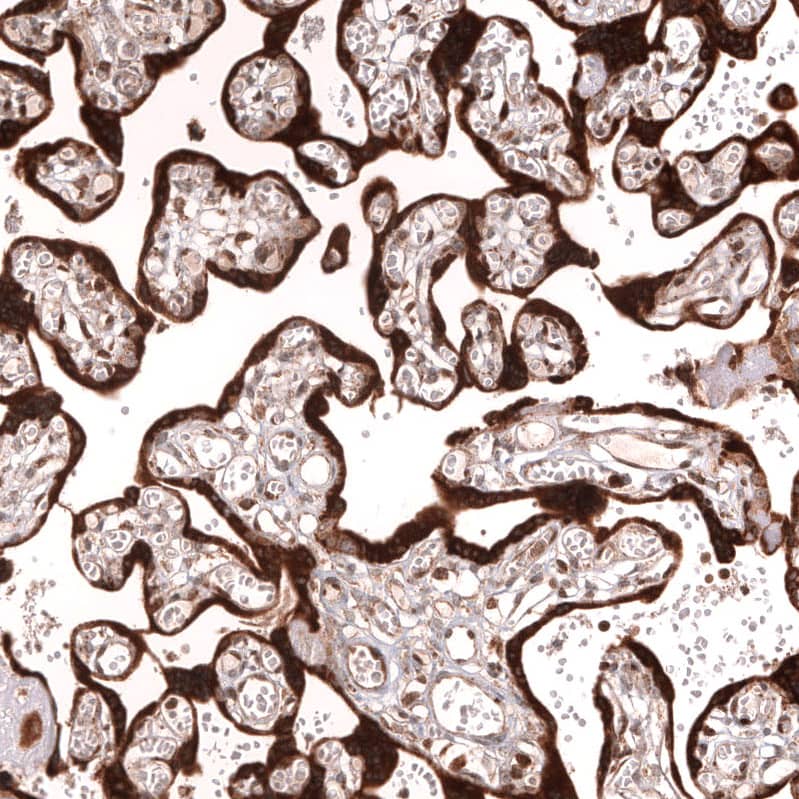

Staining of human placenta shows strong cytoplasmic positivity in trophoblastic cells.